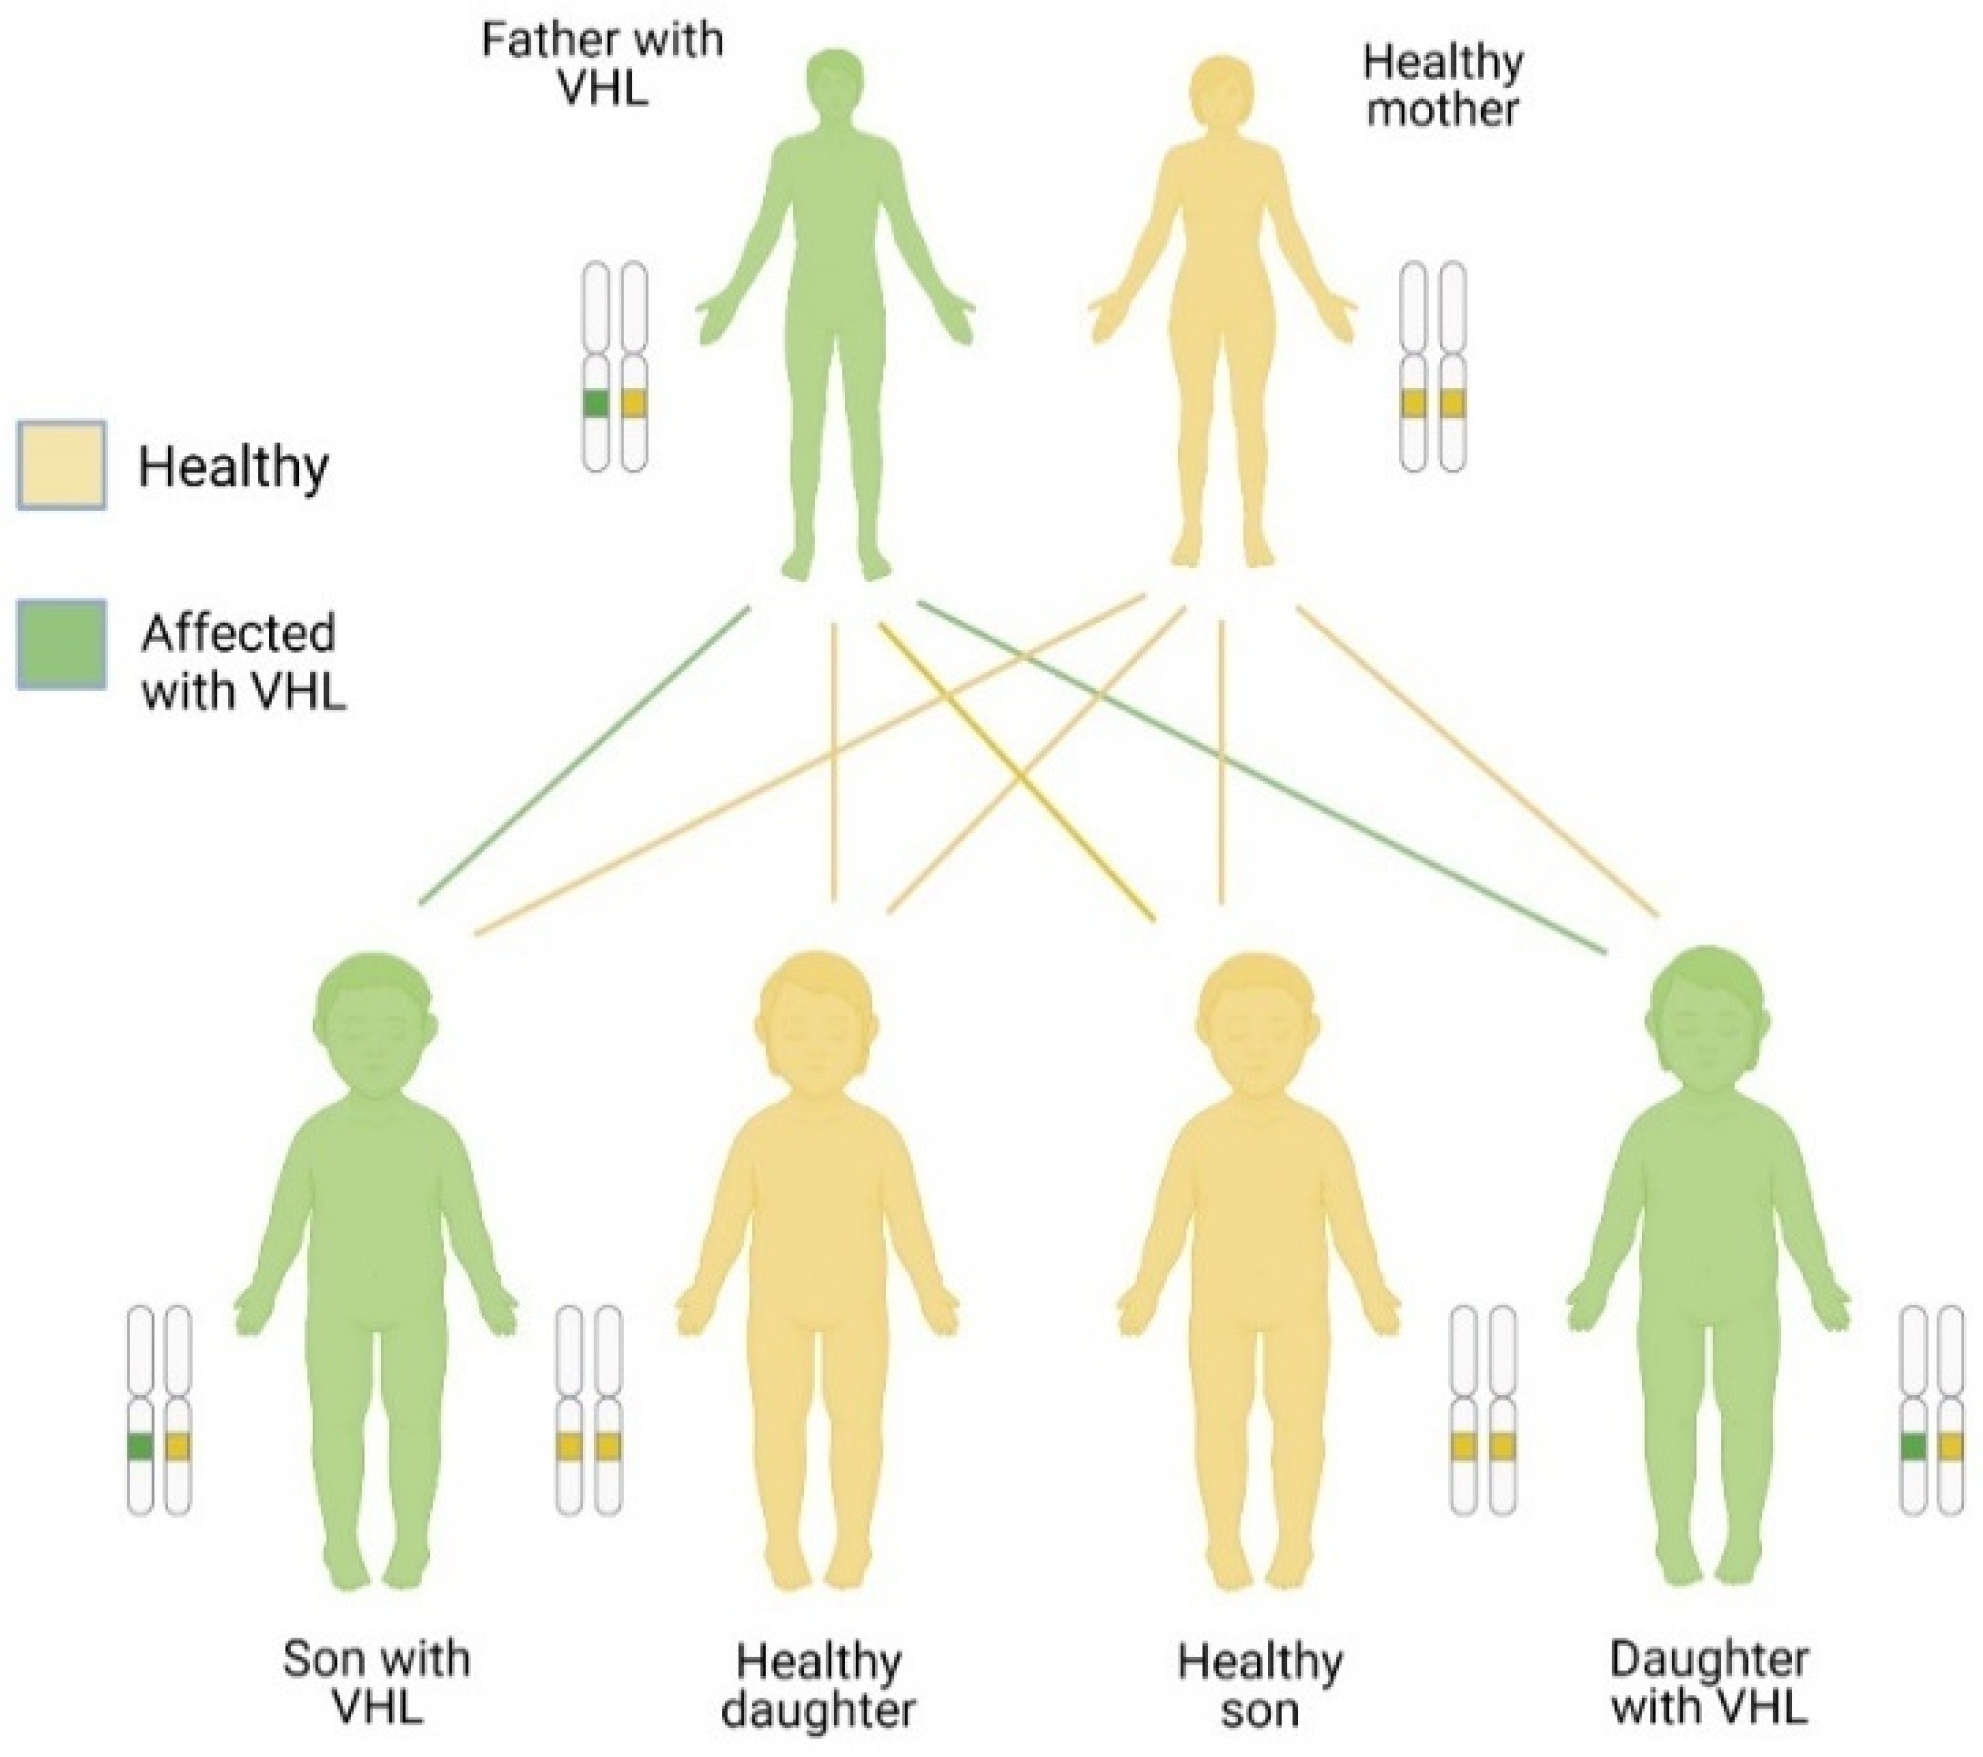

3.2. Inheritance